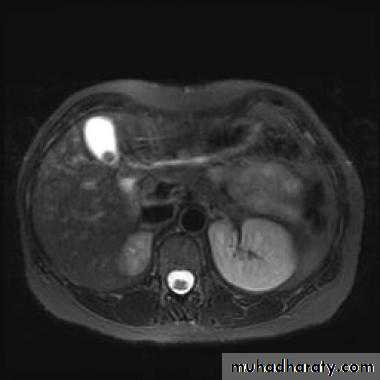

MRI : It is used as a problem-solving technique to give additional information to US and CT scan. It is a good technique for demonstrating primary and secondary tumors and is often used when surgery is contemplated. IV contrast is used to improve visualization and help characterize lesions.

At MRI, metastases typically have a signal lower than normal liver on T1 and a high signal intensity on T2.

US features of simple cyst: sharp margin, echofree, with acoustic enhancement

CT features of simple cyst: very well defined margin with water density(HU=0 – 20).

MRI features of simple cyst: low signal on T1 and high signal on T2.

Simple cyst do not show enhancement after IV contrast in CT and MRI

Magnetic resonance cholangiopancreaticography (MRCP)

MRCP technique use heavily T2-weighted sequences where bile and pancreatic ducts have high signal intensity. Unlike ERCP, it is non-invasive, does not require sedation and bowel intubation & no contrast agent used , although ERCP is necessary for any endoscopic biopsy or treatment